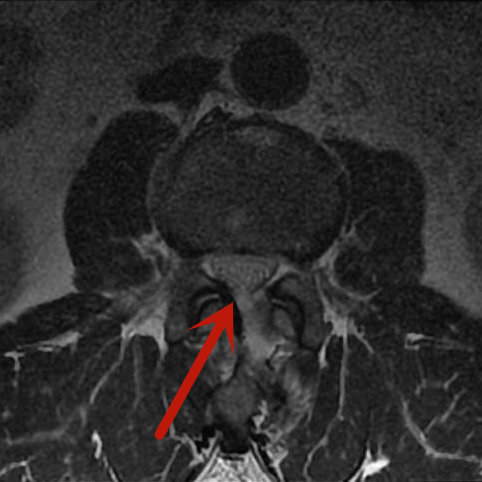

近期,梁先生因雙下肢麻木到我院脊柱骨科住院治療。腰椎磁共振檢查顯示患者的腰2-3椎管內腫瘤,很大可能性是血管瘤,若不及時手術治療,隨著腫瘤的生長、神經長時間受壓,將可能導致雙下肢癱瘓、大小便失禁等嚴重后果。

術前影像

患者腫瘤的大小約3.5cm×1.5cm,別看腫瘤不大,但要在內鏡下完全通過0.8cm大小的切口進行腫瘤后方的椎板切除減壓、腫瘤與周圍神經的分離、腫瘤的暴露、腫瘤的徹底切除,需要嫻熟的內鏡操作技術。